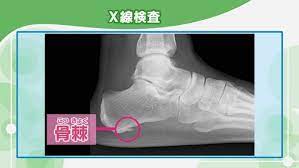

nhk健康 足の裏を押すと痛い時は要注意 足底腱膜炎の症状と治療方法とは 足底腱膜炎 足底筋膜炎 治療